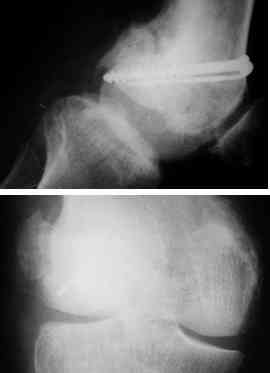

This was fixed temporarily, bone grafted with tricortical struts, and fixed by two cancellous screws. The fragment was not large enough to afford any fixation to a plate or such implant, and the screws held it compressed well to the rest of the distal femur.

Post-op - limb is well aligned, rom 0-30, but I am not pushing that right now, for the next two or three weeks.

Further plan - hope that the screws hold the fragment appropriately till union, but if the stability on table is anything to judge by, that should not be a problem.

Pictures attached.

A good job, though personally I would have preferred the screws a bit longer.